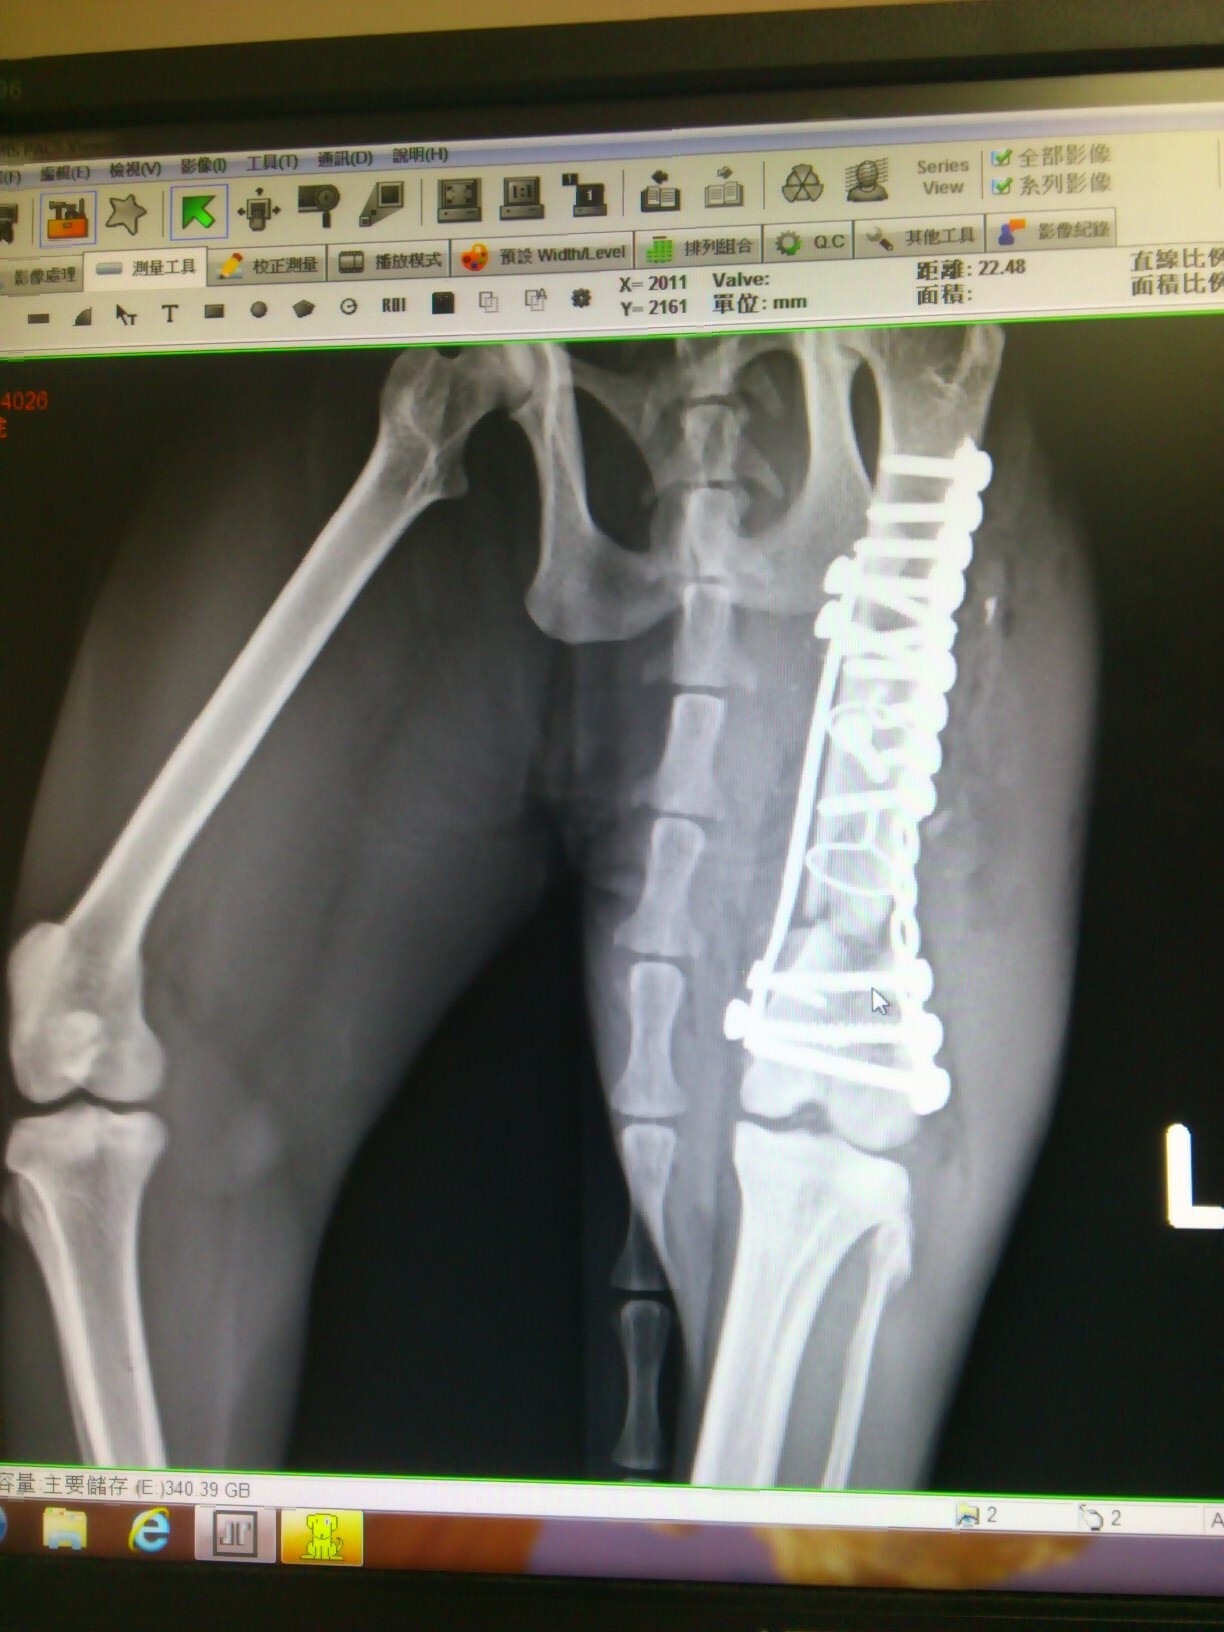

主題: 哺乳母貓車禍造成嚴重骨折 申請者姓名: 金承穎 花色: 申請日期: 2013-06-11 16:59:51 申請者部落格: 申請者臉書網址: 所在縣市/合作醫院: 台北市/其他院所醫助專案(醫院請先MAIL溝通) 治療費用: 61900元 需求人數: 64人 已結案 (2013-09-03 16:23:02) 報名人員: Jong Chia Liu x2(已付款)、吉布弟(已付款)、Katilin Chang(已付款)、momo x2(已付款)、Yin-Chia Su(已付款)、Norman Wu(已付款)、philip x2(已付款)、smilecat x2(已付款)、小節(已付款)、小麥(已付款)、suxiwen x2(已付款)、陳倩婷(已付款)、樂樂(已付款)、connie242(已付款)、Ping Hussard(已付款)、王麗惠(已付款)、莊又臻(已付款)、Wanhua Chan(已付款)、Lulu Lin、Lulu Lin(已付款)、Peggy Tseng(已付款)、韋懷思(已付款)、緣緣寶貝 x2(已付款)、Aretha Lin(已付款)、zofia(已付款)、Candy Wu(已付款)、Stephen(已付款)、Ted x2(已付款)、愛麗絲(已付款)、Ting-Ju Chen(已付款)、Rean Wu(已付款)、Gina Chen-hui Yu x2(已付款)、黃亞凡(已付款)、Sue Su(已付款)、Yuchun Chao(已付款)、joey(已付款)、Wei Lin(已付款)、蘇小優(已付款)、阿惹(已付款)、Meng-Ning Wang(已付款)、古法蘭(已付款)、古法蘭(已付款)、林嘉南(已付款)、游妃妃(已付款)、vivian(已付款)、lavinia x2(已付款)、Takeshi Kan(已付款)、kayu x2(已付款)、煎塔媽(已付款)、蔡秀芳(已付款)、家有三色喵(已付款)、Vivienne Peng(已付款)、Chen Ping、Chen Ping、Bess(已付款)、小p(已付款)、Ou Han(已付款)、 候補人員: 動物病情說明: 4/12早上10點左右.在承德路.百齡橋下發現牠.應該是被車撞..不然不會那麼嚴重.送醫發現.牠的左後肢嚴重開放性骨折,斷成數截、肝指數破表.為了保住他的腳,懇求協會幫忙協助幫忙安排就醫,虎虎到院時就有嚴重脹奶的問題,回到發現虎虎的地方,完全不見小貓蹤影,只能請醫師多注意虎虎的狀況

4/14日虎虎還是不願意進食,車禍對他的創傷甚巨,醫師緊急安置食道餵管,方便灌食補充營養,4/22日才進行大腿粉碎性骨折修復手術,數日後,虎虎的乳房脹奶發炎化膿,又進行手術清創,目前已經先出院照顧安置,虎虎的腳還需要做外包紮固定,等待他慢慢復原。